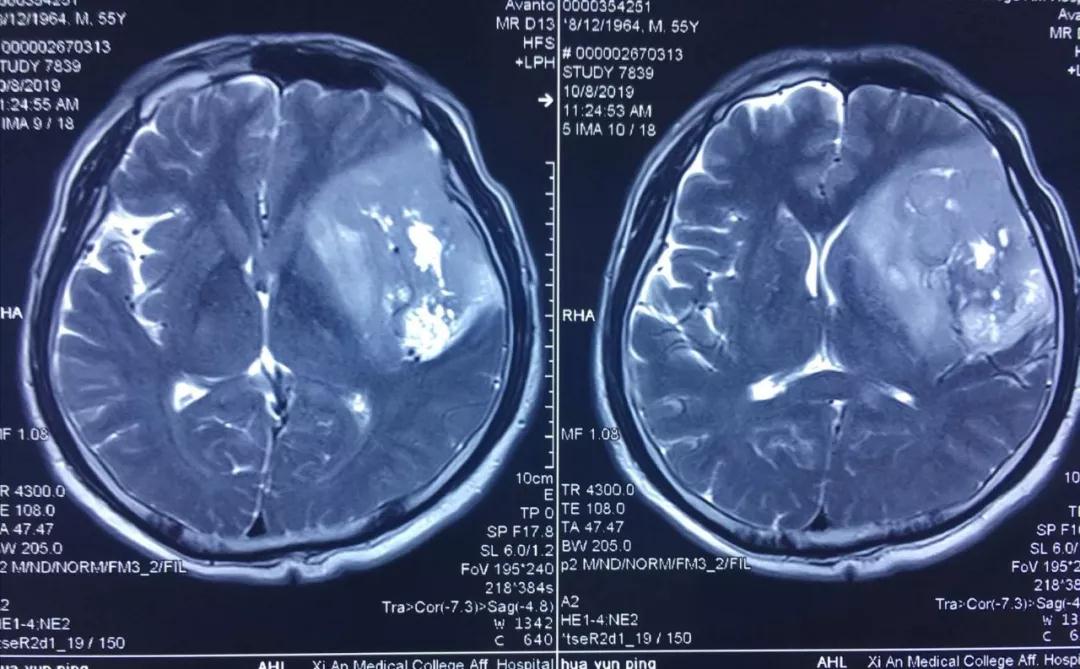

患者李某,今年55歲,因近年出現(xiàn)間歇性面部抽搐,一直未給予重視,近來(lái)發(fā)作頻繁,經(jīng)朋友建議在外院行頭顱核磁檢查,發(fā)現(xiàn)顱內(nèi)巨大占位性病變,病變位于左側(cè)額、顳和深部腦島葉,達(dá)8.5?5.5?3cm,且侵犯語(yǔ)言功能區(qū),顱內(nèi)占位效應(yīng)明顯,中線偏移1cm,且腫瘤已經(jīng)瀕臨腦疝邊緣,如不及時(shí)進(jìn)行手術(shù)干預(yù),隨時(shí)有腦疝可能,危及患者生命。

經(jīng)多方了解后,在朋友的推薦下,患者慕名來(lái)到西安國(guó)際醫(yī)學(xué)中心找到了腦科醫(yī)院高國(guó)棟院長(zhǎng),高院長(zhǎng)帶領(lǐng)以賀世明主任為首的神經(jīng)外科團(tuán)隊(duì),對(duì)患者的病情及治療方案等進(jìn)行討論,憑借多年的臨床經(jīng)驗(yàn),結(jié)合患者影像結(jié)果判斷為顱內(nèi)膠質(zhì)瘤,并建議盡快實(shí)施手術(shù)切除。